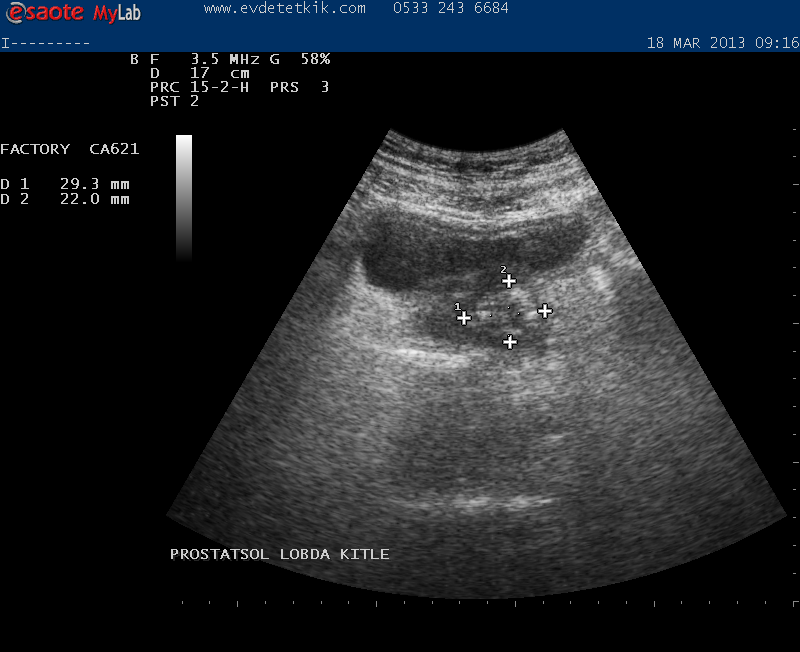

Hizmetimizden görüntüler